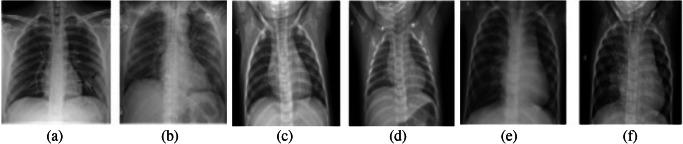

The quick spread of coronavirus disease (COVID-19) has become a global concern and affected more than 15 million confirmed patients as of July 2020. To combat this spread, clinical imaging, for example, X-ray images, can be utilized for diagnosis. Automatic identification software tools are essential to facilitate the screening of COVID-19 using X-ray images. This paper aims to classify COVID-19, normal, and pneumonia patients from chest X-ray images. As such, an Optimized Convolutional Neural network (OptCoNet) is proposed in this work for the automatic diagnosis of COVID-19. The proposed OptCoNet architecture is composed of optimized feature extraction and classification components. The Grey Wolf Optimizer (GWO) algorithm is used to optimize the hyperparameters for training the CNN layers. The proposed model is tested and compared with different classification strategies utilizing an openly accessible dataset of COVID-19, normal, and pneumonia images. The presented optimized CNN model provides accuracy, sensitivity, specificity, precision, and F1 score values of 97.78%, 97.75%, 96.25%, 92.88%, and 95.25%, respectively, which are better than those of state-of-the-art models. This proposed CNN model can help in the automatic screening of COVID-19 patients and decrease the burden on medicinal services frameworks.

冠状病毒病(COVID-19)的迅速传播已成为全球关注的问题,截至2020年7月,确诊患者已超过1500万。为了应对这种传播,临床成像,例如X光图像,可用于诊断。自动识别软件工具对于利用X光图像筛查COVID-19至关重要。本文旨在从胸部X光图像中对COVID-19患者、正常人和肺炎患者进行分类。因此,本文提出了一种优化卷积神经网络(OptCoNet)用于COVID-19的自动诊断。所提出的OptCoNet架构由优化的特征提取和分类组件组成。灰狼优化器(GWO)算法用于优化训练CNN层的超参数。利用一个公开可用的COVID-19、正常人和肺炎图像数据集,对所提出的模型进行了测试,并与不同的分类策略进行了比较。所提出的优化CNN模型的准确率、灵敏度、特异性、精确率和F1分数分别为97.78%、97.75%、96.25%、92.88%和95.25%,优于现有模型。所提出的CNN模型有助于自动筛查COVID-19患者,并减轻医疗服务系统的负担。